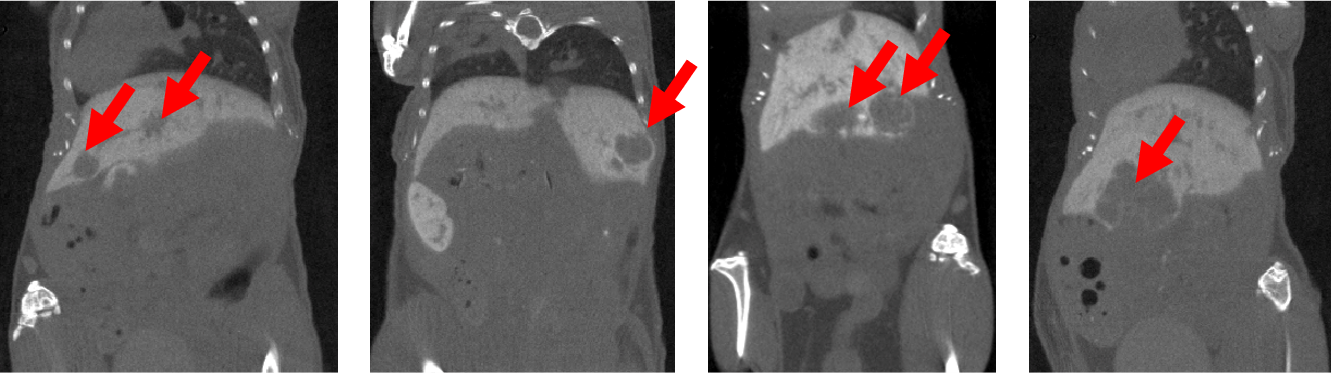

6、Contrast-enhanced tumor CT imaging

Tumor study: Contra-enhanced CT was used to examine liver tumors in living mice: Exitron 12000 was injected, FDK was reconstructed, and the imaging time was 4min, 100µm voxel size.